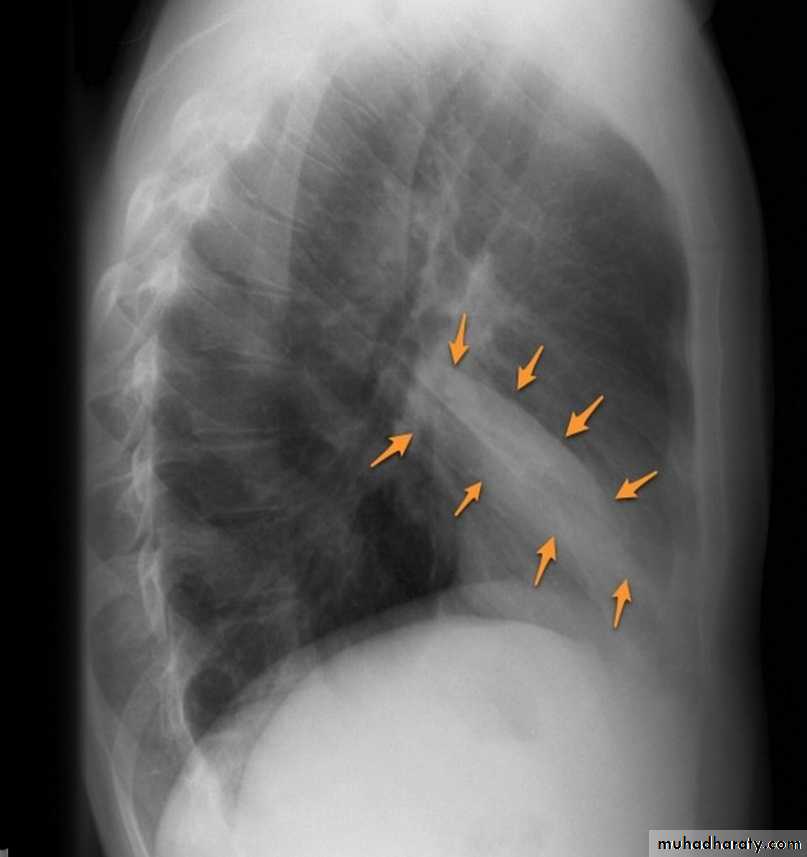

The oblique fissures are often seen on a normal lateral view .

This cut-out of a lateral chest x-ray shows the positions of the lobes of the right lung

On the left the oblique fissure is in a similar position but there is usually no horizontal fissure, and so there are only two lobes on the left.

On lateral projections the left lower lobe is hyperexpanded and the oblique fissure displaced anteriorly. There is associated increase in the retrosternal opacity.

On lateral projection the left hemidiaphragmatic outline is lost posteriorly and the lower thoracic vertebrae appear denser than normal (they are usually more radiolucent than the upper vertebrae) .